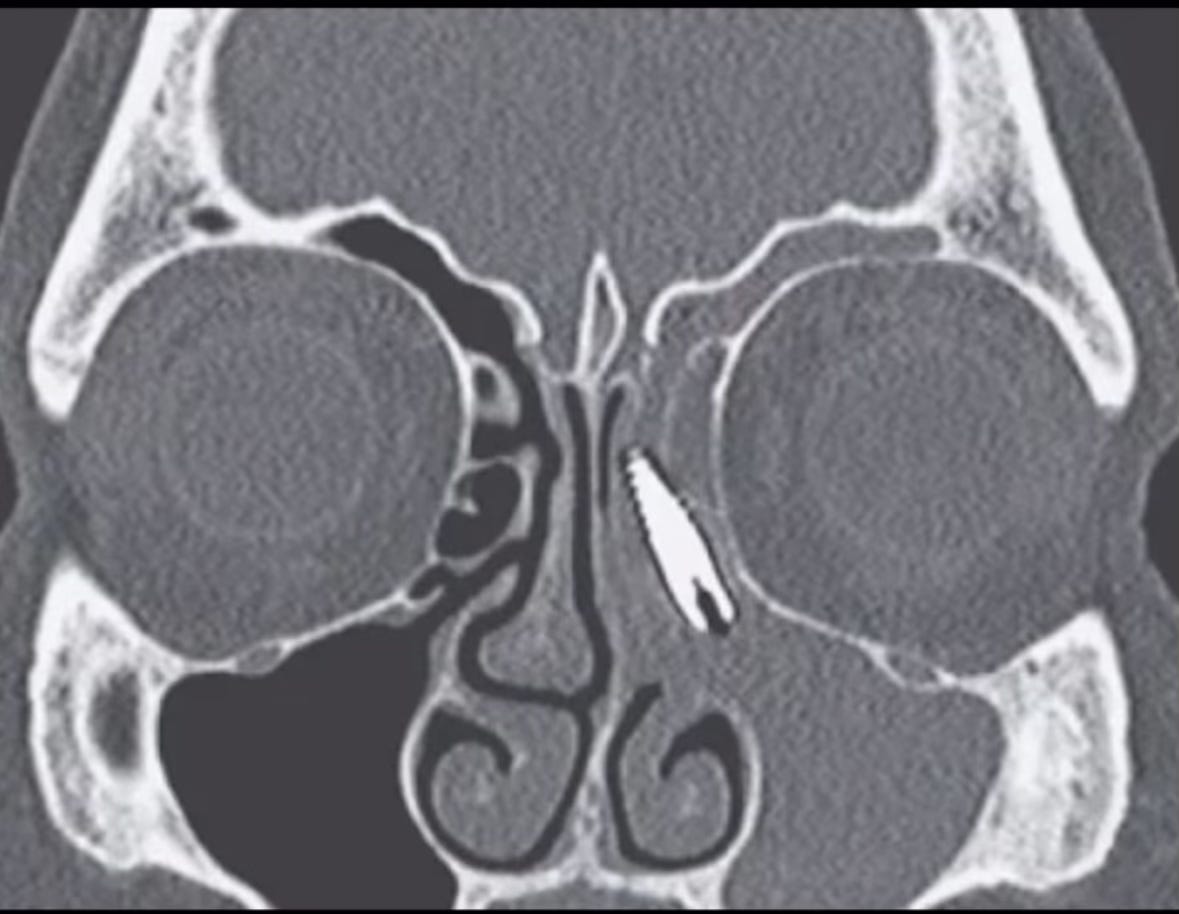

Fig.2: Secțiune CT ce arată un implant unidentar endo-osos care a migrat prin sinusul maxilar catre unghiul intern al ochiului. Inflamația sinusului maxilar este obiectivabilă datorită radio-opacității crescute pe care acesta o are, prin comparație cu cel de pe partea contralaterală.